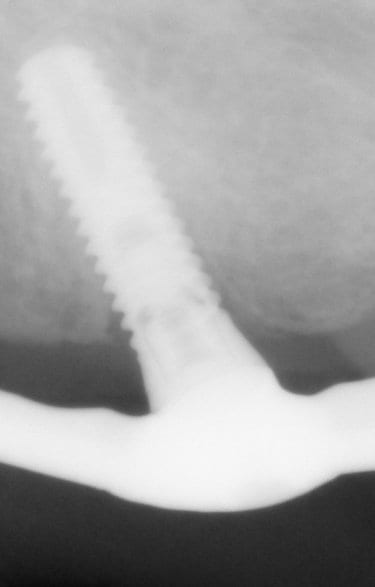

non, et pour plusieurs raisons: les spires du swissplus sont en reverse buttress et au niveau de la plateforme prothétique c'est un biseau à 45°

là les spires sont plutôt en buttress et c'est complètement plat sur la plateforme prothétique

il y a une pièce vissée dans l'implant pour transformer cette connexion interne en multiunit...et ce système, je ne l'avais encore jamais vu!

Il s'agirait finalement d'implants Tekka progress (?)